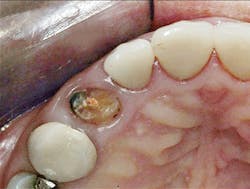

3. All supragingival coronal tooth structure gone. Endodontic treatment usually necessary. Post and core placed. Enough remaining tooth structure to allow at least 2 mm of ferrule around the margin portion of the tooth preparation, or bony crown lengthening accomplished allowing the ferrule. Nonabusive occlusion (Figures 1 and 2)-This clinical situation requires in-depth informed consent from the patient, since saving the tooth is expensive and the long-term success of the clinical result is questionable. If the treatment fails, an extraction, along with an implant and crown or a fixed prosthesis, will be required, further adding to the patient cost. The potential for success is markedly reduced in this situation. However, proper placement of a post and core and crown allows clinical success in a significant percentage of cases. If the patient feels more comfortable with an implant after proper informed consent, that treatment should be strongly considered. However, in my experience, many patients prefer to retain the affected tooth, in spite of the reduced potential for long-term service. That is also my personal preference.